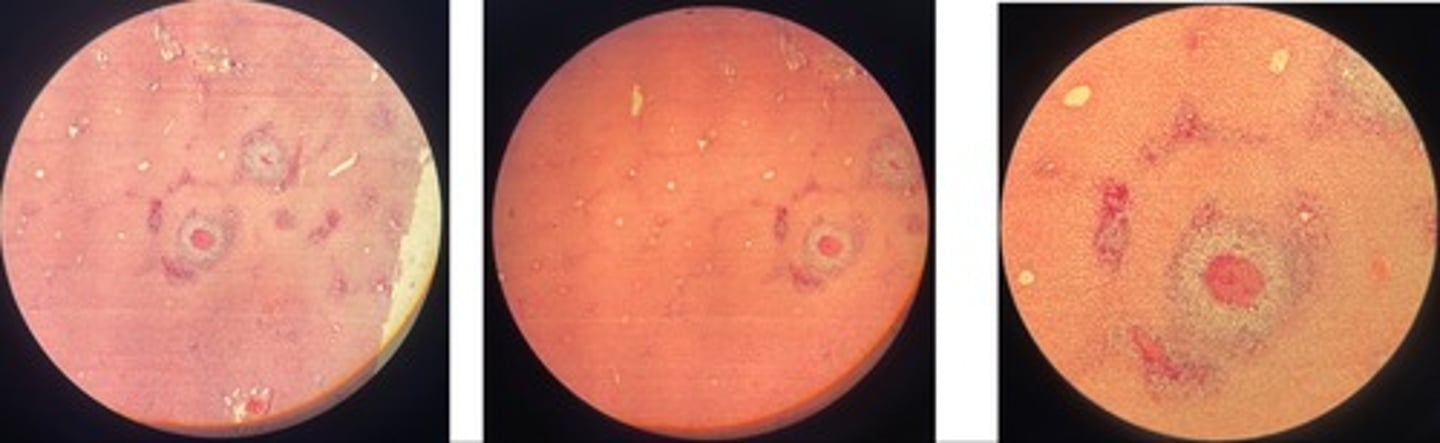

Hepatic coccidiosis … intracell parasites

- dilated bile ducts

- hyperplasia of biliary epi => papillary projections

- oocysts in lumen + inflam cells

- atrophy + degen

Hepatic echinococcus

- cystic structure lined with chitin mem

- may have protoscolices (parasite larvae)

- liver parenchyma => atrophy, fatty degen, necrosis, haemorrhage

- infiltrate cells: macrophages, epitheliod cells and giant cells